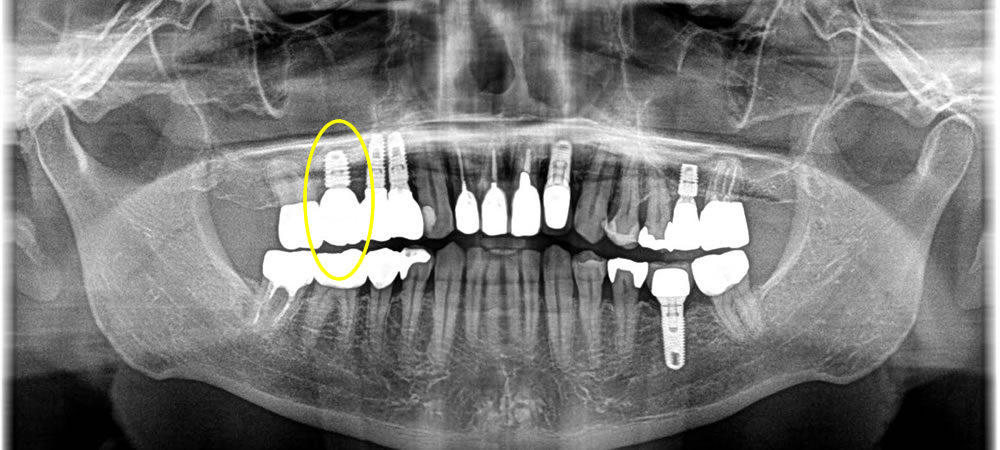

痛む歯を抜歯してインプラントで治療した症例

こちらの患者さまはインプラントの後ろの歯が痛いとの事で治療を開始しました。

上部の銀歯を除去したところ、中の歯が虫歯と破折により保存する事ができなくなっていました。

手前にインプラントが入っているため、できるだけ歯茎が下がらないように治療をする事と、CT写真にて上顎洞までの骨の厚みが無い事がわかったので、まずは歯を抜いて骨が落ち着くまで4ヵ月待ちインプラントオペを行う事にしました。

今回は上顎洞までの骨の厚みが足りなかった為に上顎洞粘膜を挙上し、骨を作ると同時にインプラント体を埋入していきました。粘膜を挙上する方法としては水の圧力を利用して行っていきました。

そこから5ヵ月おき、骨の吸収が無く、骨とインプラント体がオステオインテグレーションしている事を確認し、上部に歯を作成していきました。

結果、横の歯の歯茎が下がりインプラント体が見える事なくしっかりとした歯を作成する事ができました。